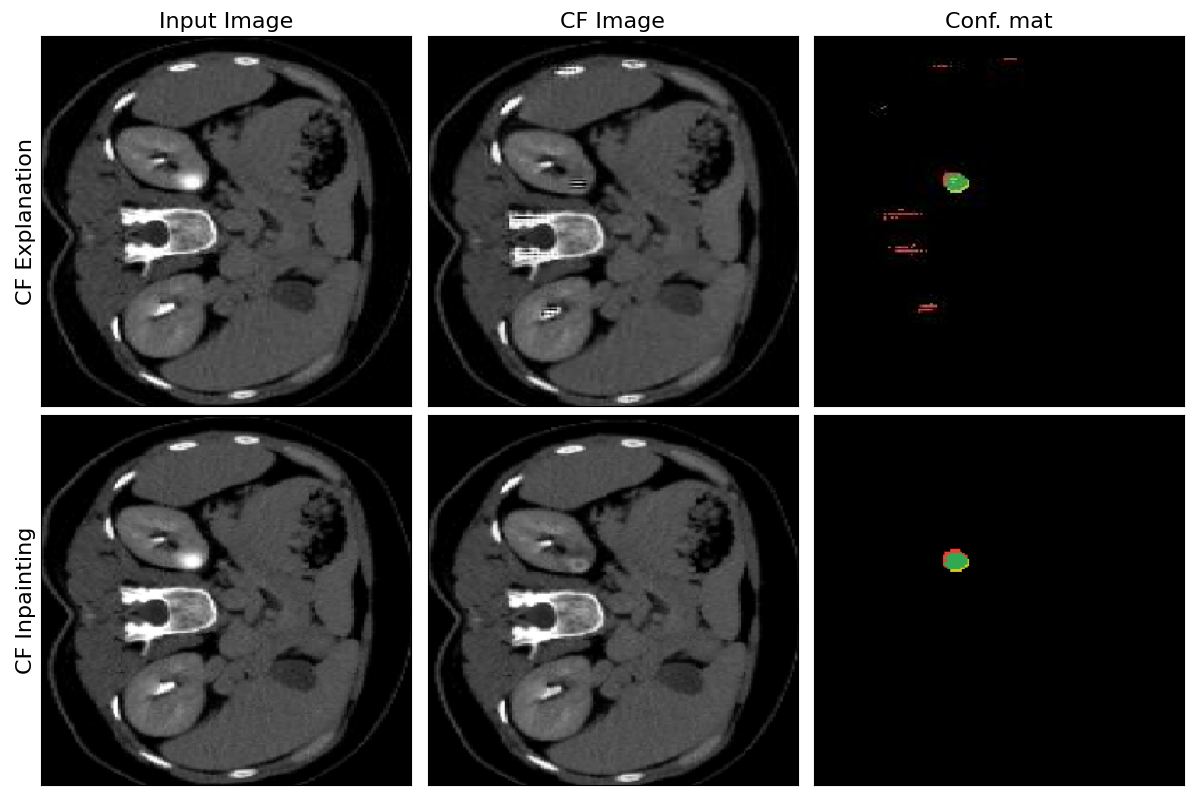

7.5 Counterfactual Explanation vs Counterfactual Inpainting Segmentation Accuracy

Refer to caption

Figure 6: Examples of images generated with perturbation-based Singla et al.* method equipped with skip connections and with the proposed counterfactual inpainting approach.

This experiment proves that the proposed counterfactual inpainting pipeline outperforms the base counterfactual explanation approach. Both methods are trained and evaluated in terms of segmentation accuracy for the extracted weak segmentation labels from the counterfactual images.

The benefits of using the counterfactual inpainting are two-fold. First, it does not require segmentation masks for enforcing local consistency. Second, the IoU score is much higher due to the fact that the model is simplified to only either inpaint the anomaly or not to produce the segmentation mask. Figure 6 gives qualitative evaluation of the generated counterfactuals following the two approaches.